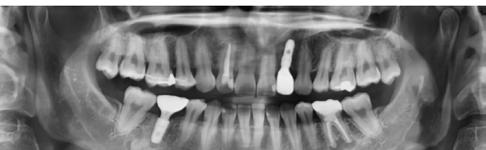

5. ábra: Dr. Chun esete. Dentium Narrow implantátumok és azok protetikai ellátása 4 hónappal a beültetést követően.

6. ábra: Dr. Lim esete. Dentium Narrow implantátumok a felső állcsonton, guide tervezés, ideiglenes hídpótlás azonnali terheléssel, majd 4 hónappal később végleges protetikai ellátás.

7. ábra: Dr. Byun esete. Keskeny állcsontgerinc a jobb alsó és mindkét oldali felső laterális régióban. Implantáció Dentium Narrow implantátumokkal, majd 4 hónap múlva protetikai ellátás.

8. ábra: Dr. Chang esete. 2.4-es fog helyén keskeny gerinc. Csontpótlással együtt Dentium Narrow implantátum behelyezése. 4 hónap múlva korona készítése.